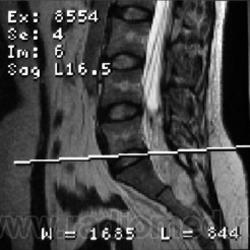

ГМ. СМ. Эпендимома миксопапиллярная. +

Эпендимома миксопапиллярная